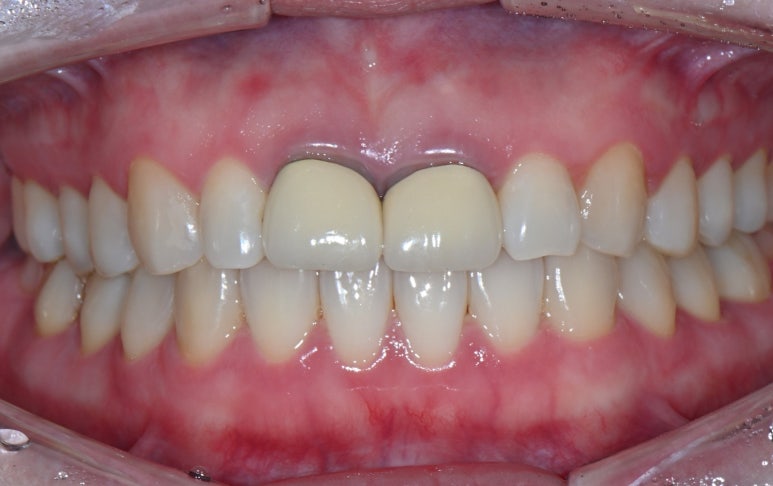

3. 임시치아 장착 & 잇몸 적응 확인

기존 크라운을 제거한 날, 치아를 다듬고 기공소에서 제작한 임시치아를 장착합니다.

그리고 신경치료를 진행하는 동안 중간중간 잇몸이 새로운 크라운 형태에 잘 적응하는지 체크했습니다.

약 3주의 기간 동안 크라운 주변 잇몸이 잘 적응한 것을 확인 할 수 있었습니다.

25.08.11 임시치아 장착

25.09.04 임시치아 장착 약 3주 후